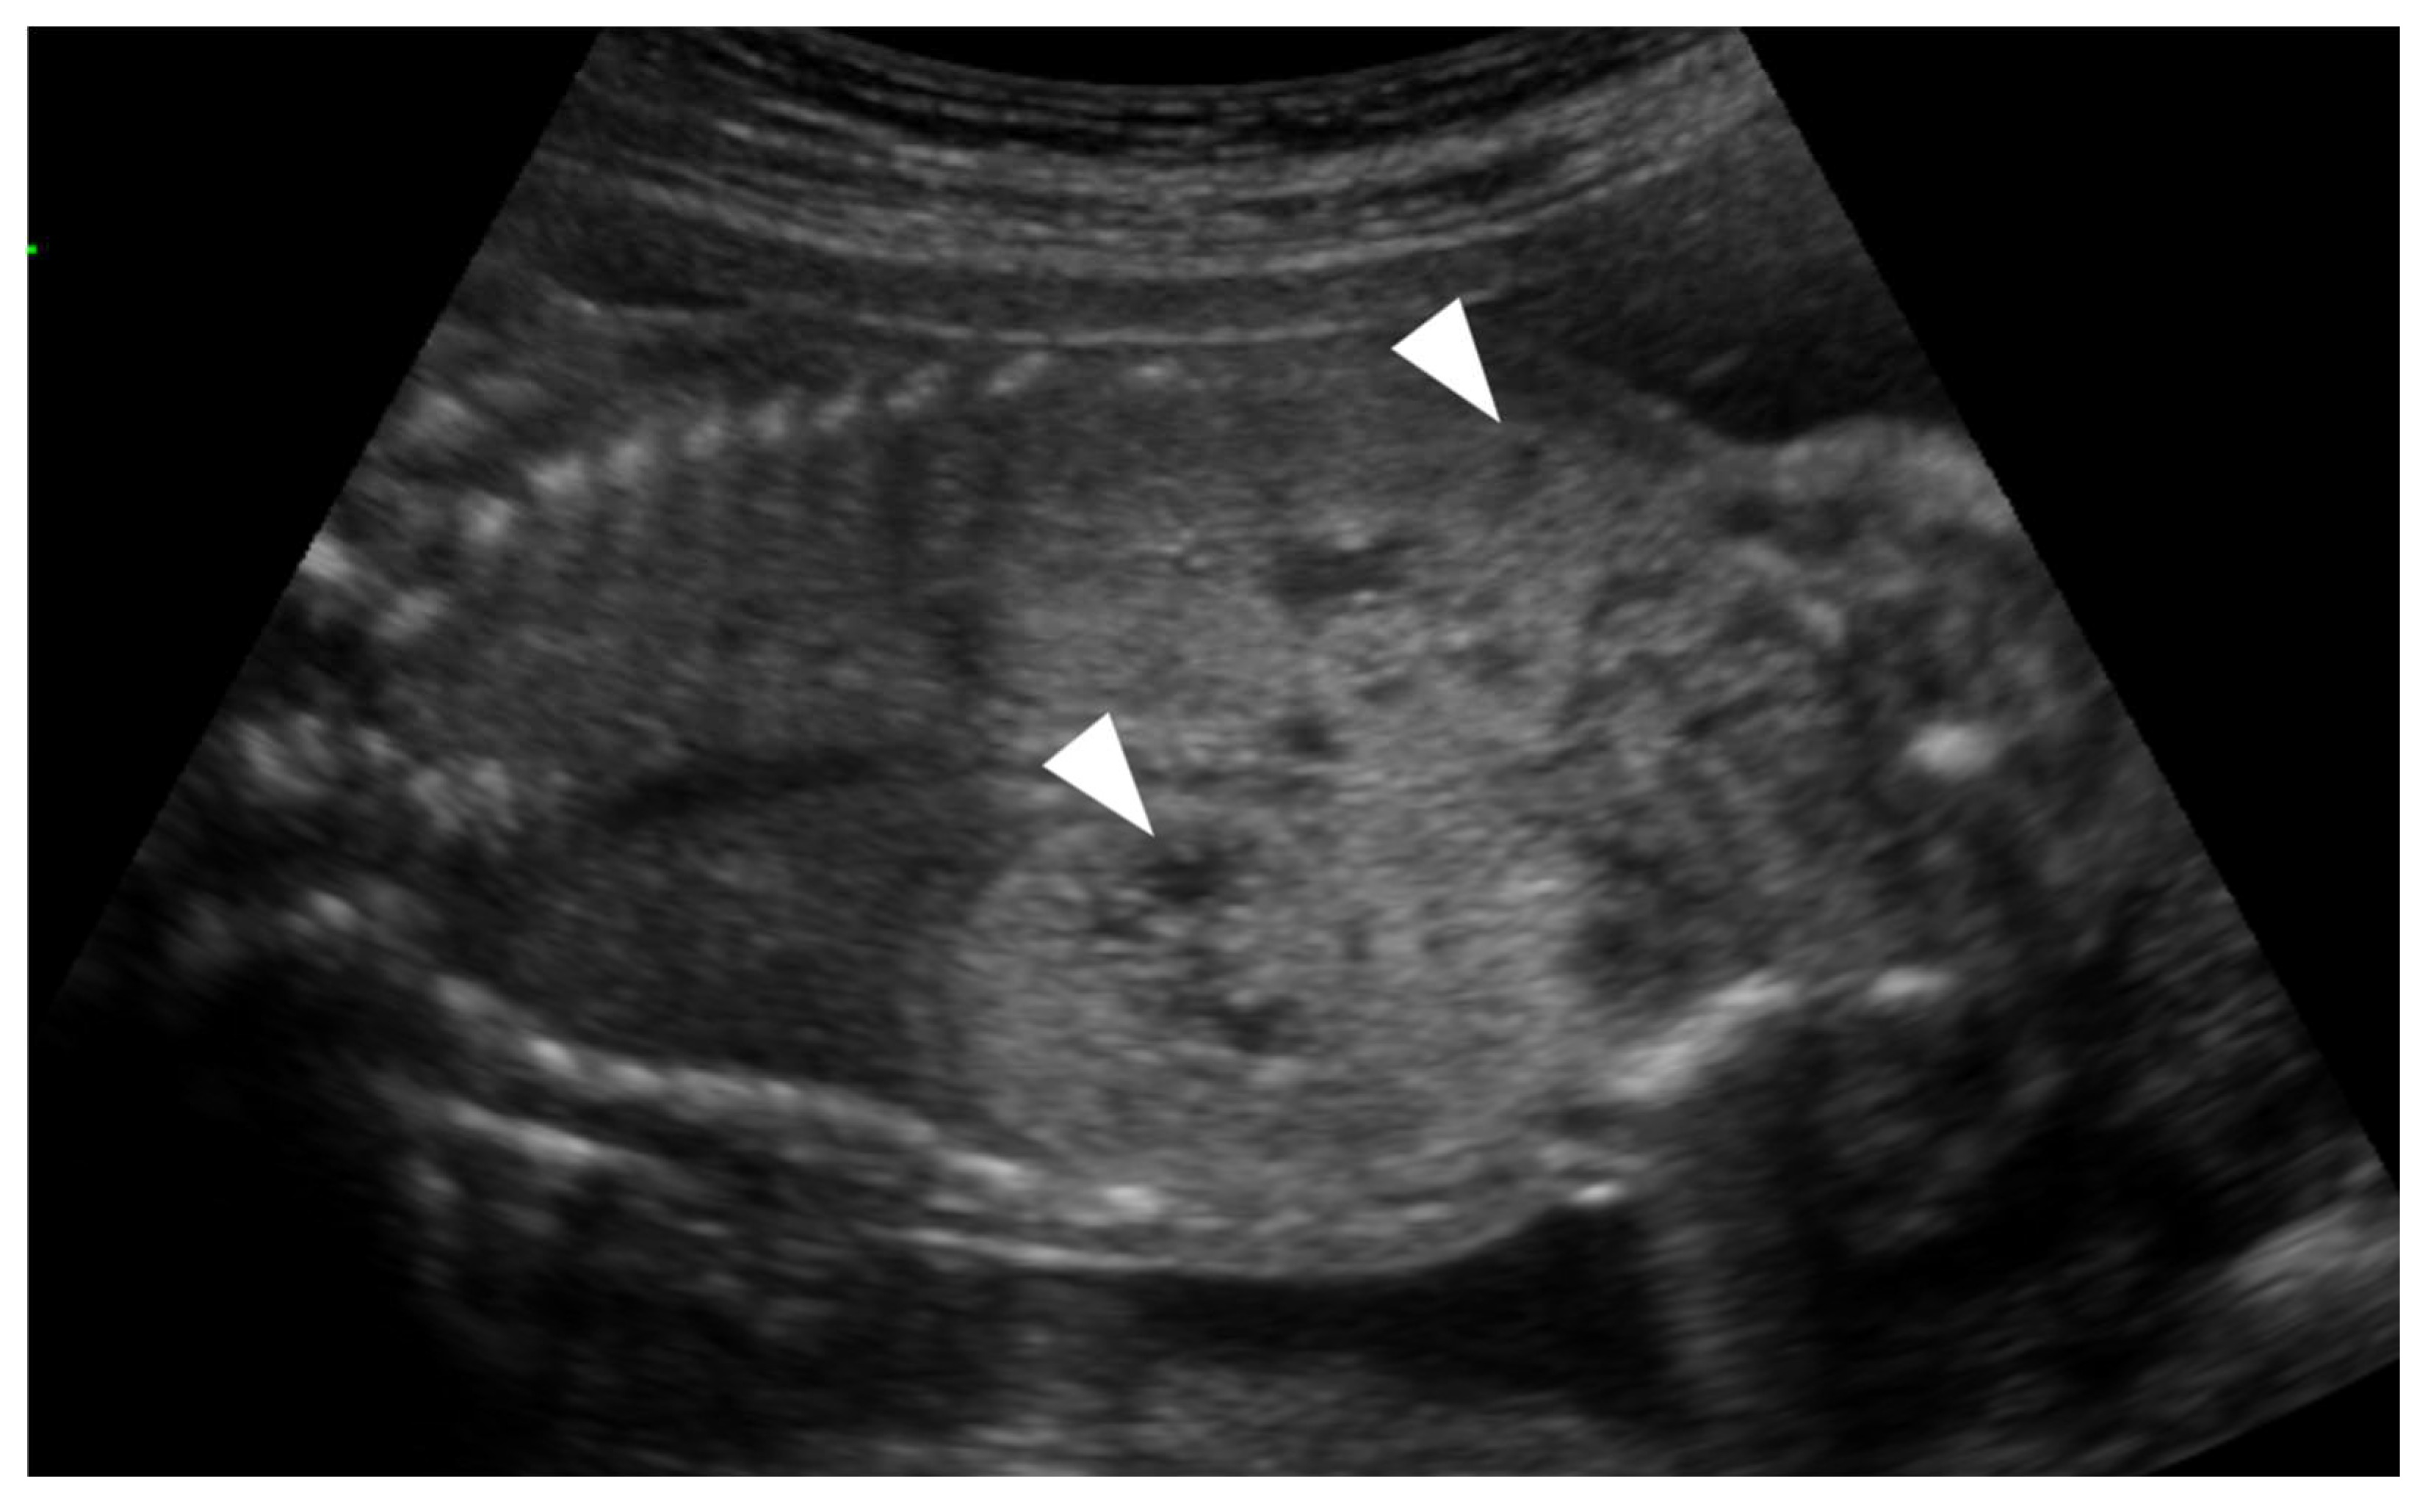

- Brun, M.; Maugey-Laulom, B.; Eurin, D.; Didier, F.; Avni, E.F. Prenatal sonographic patterns in autosomal dominant polycystic kidney disease: A multicenter study. Ultrasound Obstet. Gynecol. 2004, 24, 55–61. [Google Scholar] [CrossRef]

- Garel, J.; Lefebvre, M.; Cassart, M.; Della Valle, V.; Guilbaud, L.; Jouannic, J.M.; Ducou le Pointe, H.; Blondiaux, E.; Garel, C. Prenatal ultrasonography of autosomal dominant polycystic kidney disease mimicking recessive type: Case series. Pediatr. Radiol. 2019, 49, 906–912. [Google Scholar] [CrossRef]

- Gupta, A.; Aneja, A.; Bahl, N.; Arora, R.; Nadir, L.; Saini, P. Corticomedullary differentiation in fetal kidneys: A necessary evil? J. Fetal Med. 2024, 11, 139–144. [Google Scholar] [CrossRef]

- Buffin-Meyer, B.; Klein, J.; Aziza, J.; Fernandez, M.; Feuillet, G.; Seye, M.; Buléon, M.; Fédou, C.; Camus, M.; Burlet-Schiltz, O.; et al. Improved prenatal assessment of kidney disease using multiple ultrasound features. Nephrol. Dial. Transplant. 2025, 40, 341–351. [Google Scholar] [CrossRef]

| Increased renal size (>97 percentile) | 7 (35.0%) |

| Increased cortical echogenicity | 17 (85.0%) |

| Presence of cortical cysts | 9 (45.0%) |